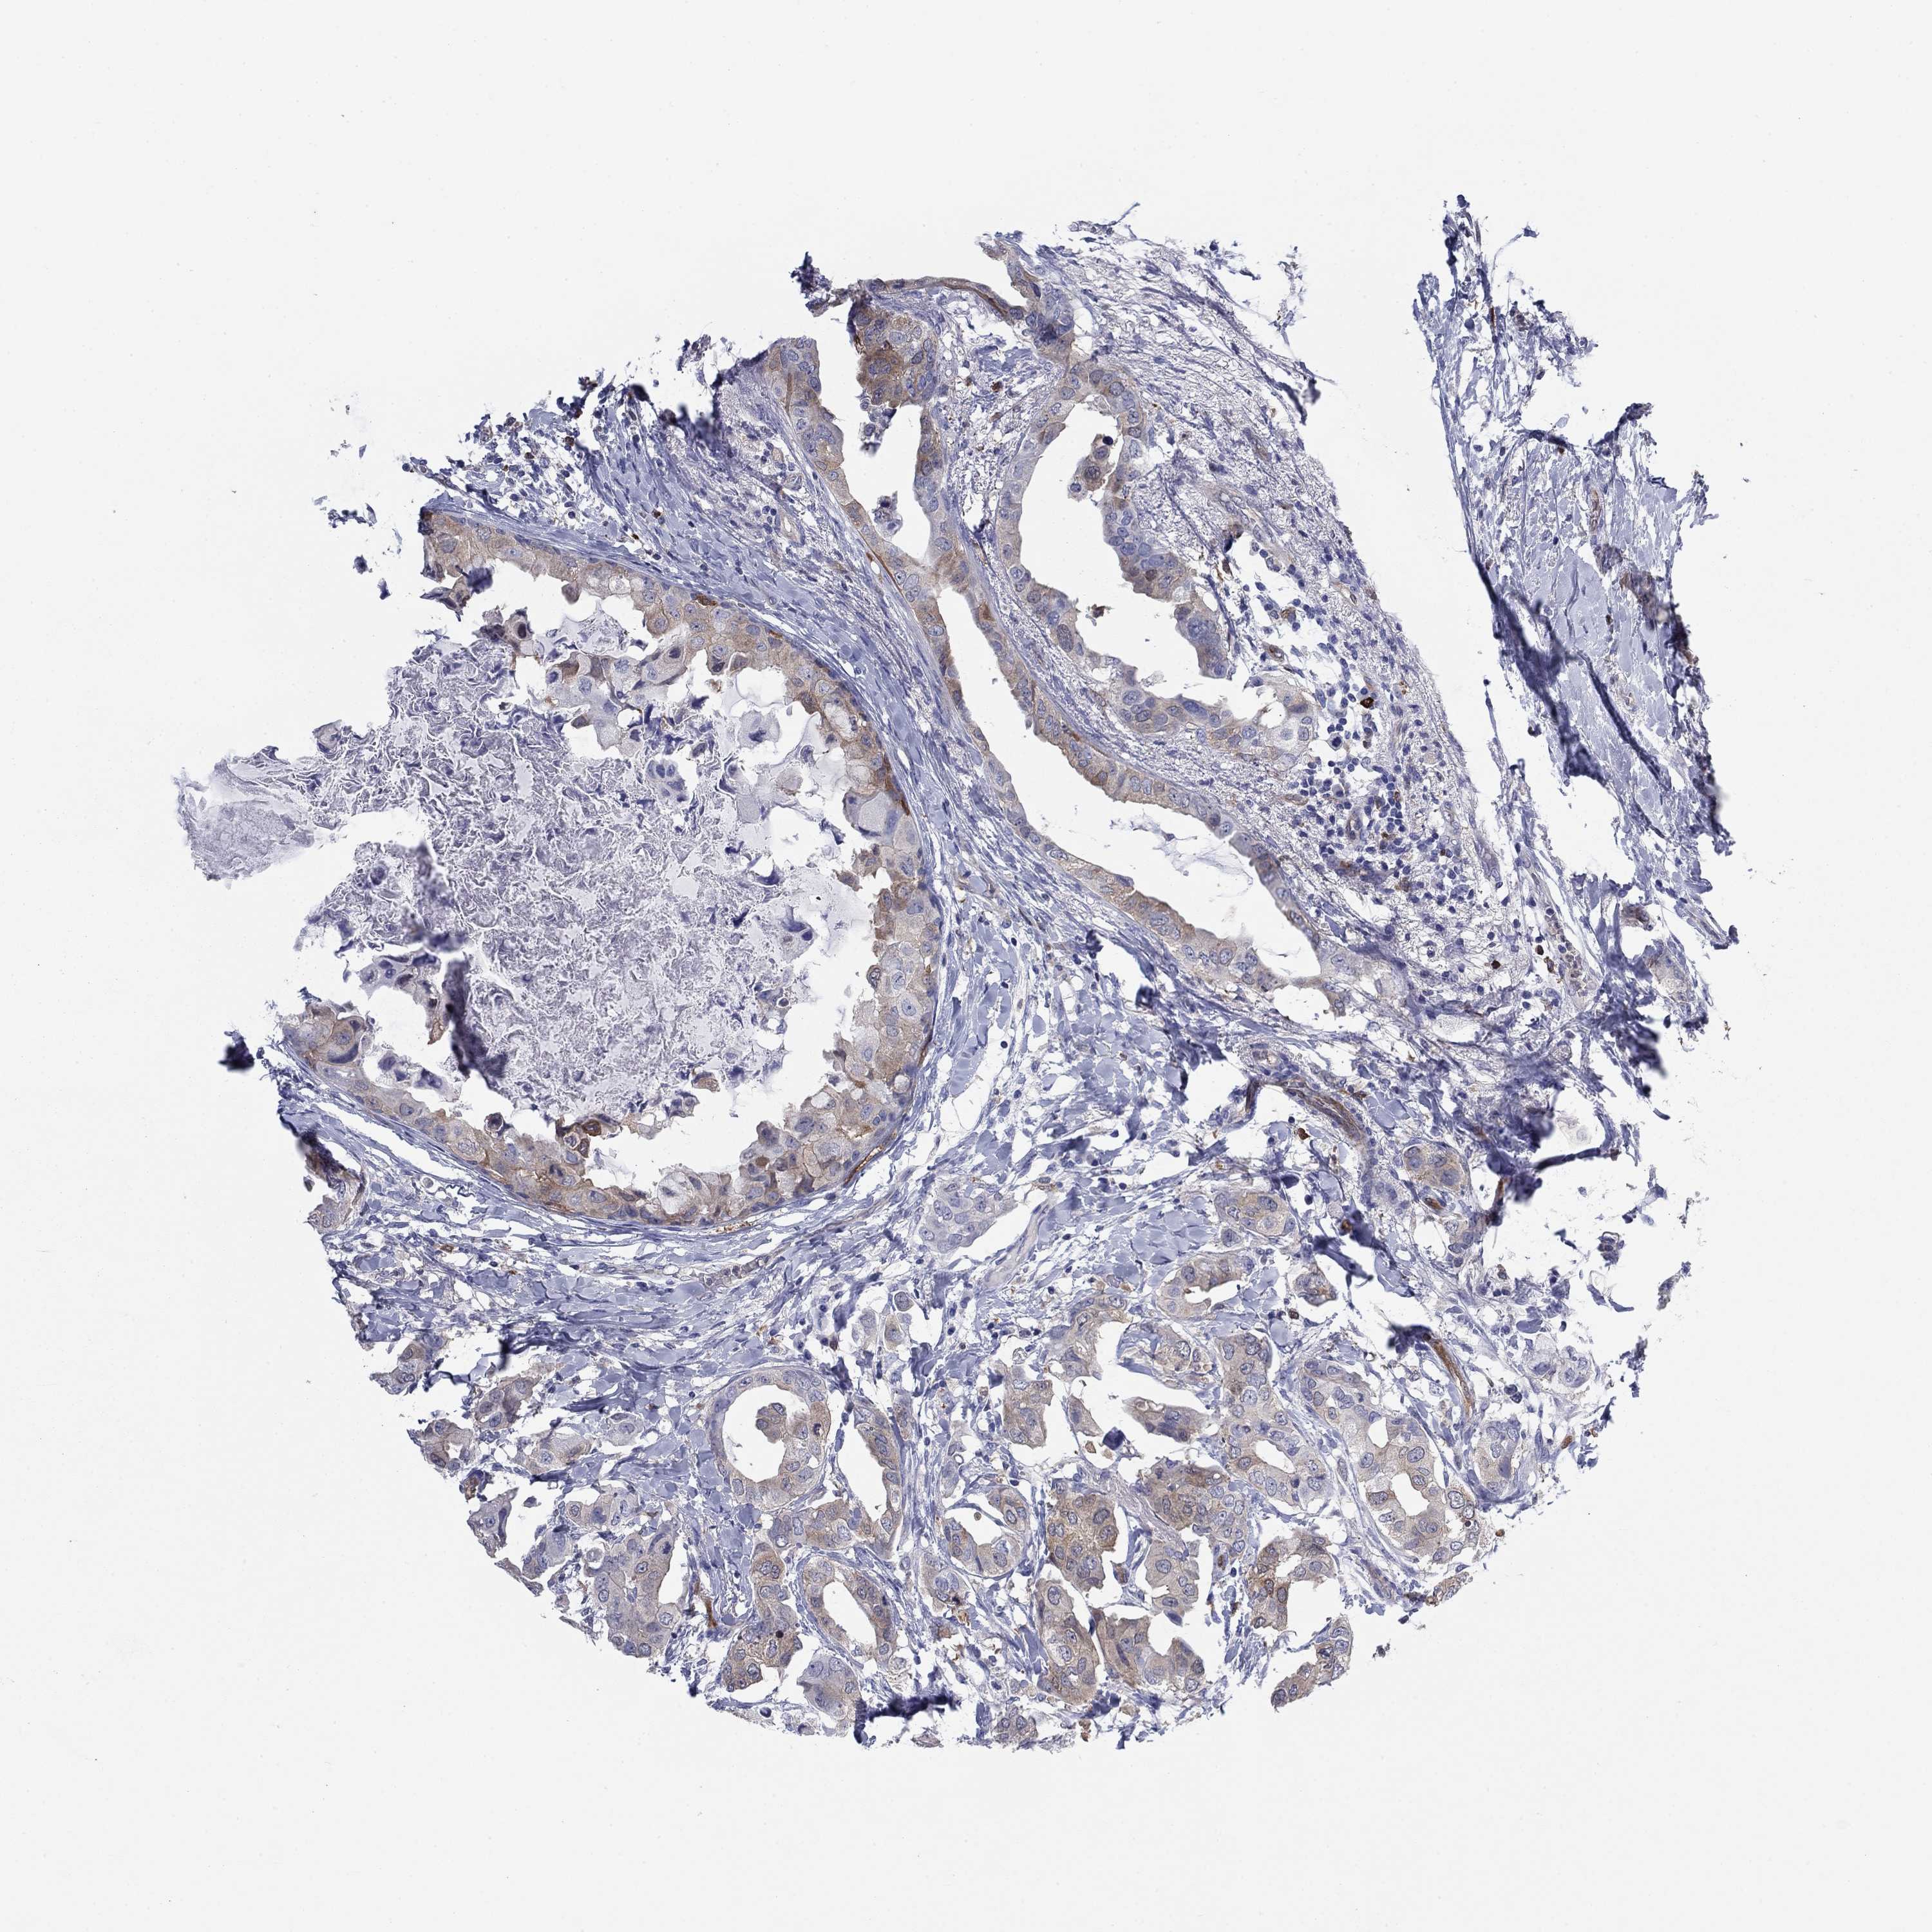

BRCA TCGA BRCA VALIDATION PROTEIN EXPRESSION

ANTIBODIES

AND

VALIDATION